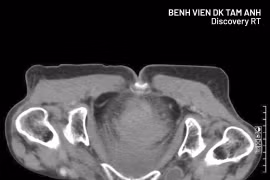

Cụ bà 77 tuổi nguy kịch vì thoát vị bịt

Khi xuất hiện các biểu hiện như đau bụng, nôn mửa, đặc biệt ở trẻ em và người cao tuổi, người bệnh nên đến viện sớm, tránh bỏ sót những bệnh lý nguy hiểm.